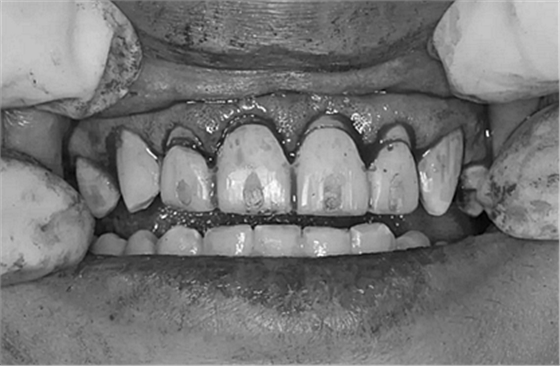

第5次復診的時候,終于讓我們4個兄弟恢復了正常的容顏。

現(xiàn)在剩下的任務就是為我其他的兄弟姐妹們治療了。需要做根管的做根管,需要做冠的做冠,需要樹脂充填的做樹脂充填。前前后后主人帶我們進行了12次的復診,歷時6個月,現(xiàn)在的我們是這樣的

再來看看曾經(jīng)的我們